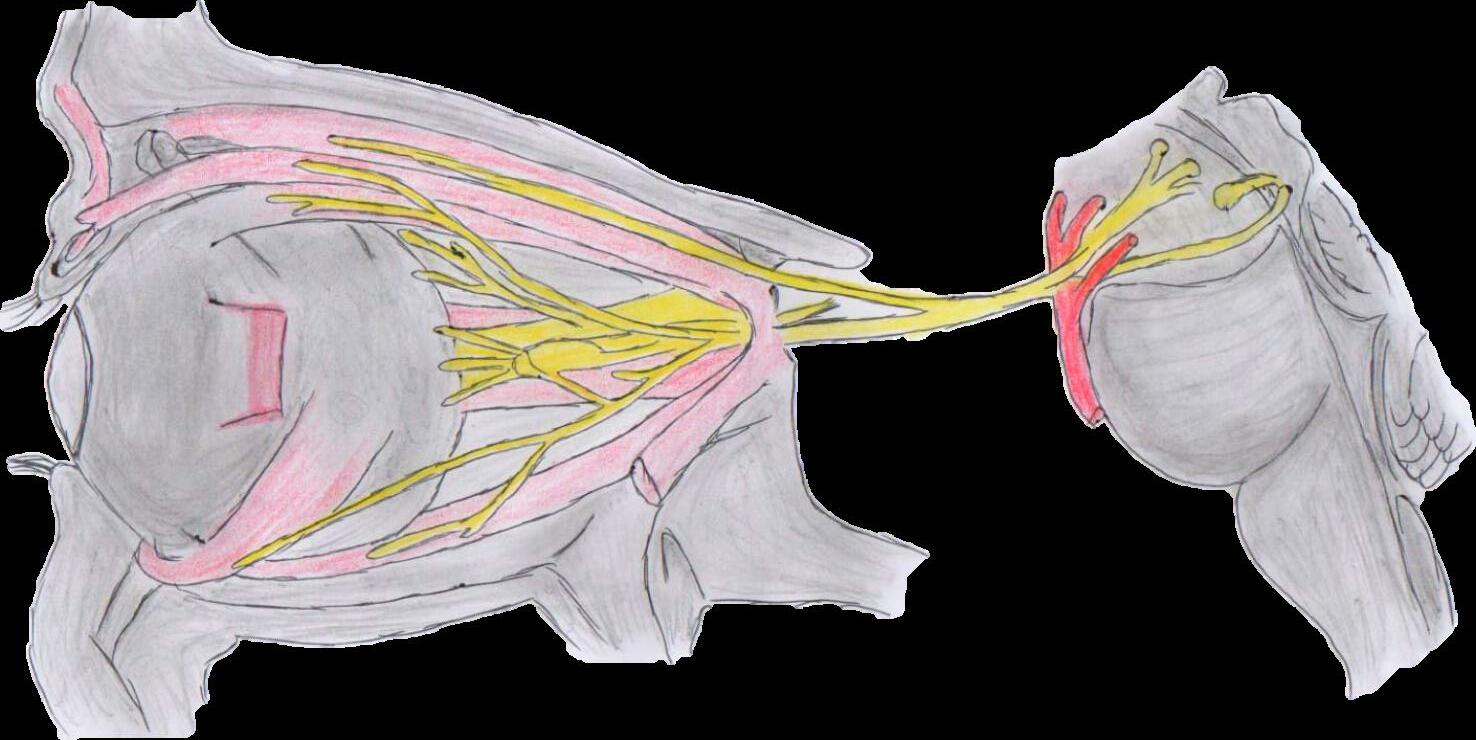

NERVIO OCULOMOTOR (III PAR)

Características

Se encarga del movimiento de los ojos, elevacion del parpado, contraccion pupilar.

Musculo oblicuo superior

Musculo recto superior Musculo elevado al parpado superior

Nervio troclear

Rama superior del nervio oculomotor

NERVIO OCULOMOTOR

Arteria carótida interna

Iris

Nervio trigémino

Musculo oblicuo inferior

Musculo recto inferior

Ganglio ciliar

Rama inferior del nervio oculomotor

NERVIO TROCLEAR (IV PAR)

Musculo obliquo superior

Arteria cerebral posterior

Nervio troclear (IV)

Características

Su funcion es el movimiento de los ojos arriba y abajo.

Arteria cerebral superior

Nervio oculomotor (III)

NERVIO TRIGÉMINO Rama oftálmica Rama maxilar Rama mandibular NERVIO ADBUCENTE Nervio vestibulococlear Nervio facial Nervio trigémino Nervio troclear Nervio oculomotor Quiasma óptico Musculo recto superior Musculo oblicuo superior Tróclea Musculo elevador del parpado superior Musculo oblicuo inferior Musculo recto inferior Ganglio ciliar Musculo recto medial Musculorectolateral NERVIO ABDUCENTE (VI PAR) NERVIO TRIGEMINO (V PAR)

Controla principalmente la musculatura de la masticacion y la sensibilidad facial.

lEs el responsable del giro del ojo hacia afuera.

Características

Características